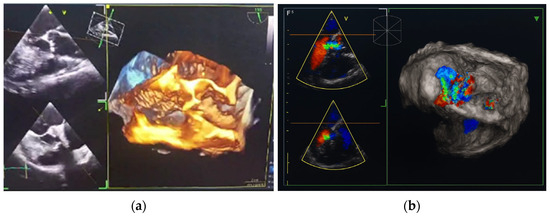

Background/Objectives: Cardiovascular diseases (CVDs), including valvular heart disease (VHD), remain the leading cause of morbidity and mortality in patients with rheumatoid arthritis (RA) and systemic lupus erythematosus (SLE). Case Presentation: We report a rare case of a woman in her fifth decade of [...] Read more.

Background/Objectives: Cardiovascular diseases (CVDs), including valvular heart disease (VHD), remain the leading cause of morbidity and mortality in patients with rheumatoid arthritis (RA) and systemic lupus erythematosus (SLE). Case Presentation: We report a rare case of a woman in her fifth decade of life diagnosed with overlap syndrome (RA and SLE), in whom transthoracic echocardiography (TTE) and transesophageal echocardiography (TEE) revealed a degenerative altered bicuspid aortic valve with moderate aortic regurgitation (AR) and preserved left ventricular systolic function. The patient presented with a recent history of continuous, moderate chest discomfort and progressive exertional dyspnea, along with a mild elevation in highly cardioselective enzymes. AR was confirmed as the cause of her symptoms, rather than acute coronary syndrome or heart failure. Conclusions: This case highlights the potential contribution of chronic systemic inflammation in RA/SLE to the pathogenesis of AR, an extra-articular manifestation associated with adverse clinical outcomes. These findings support the routine use of echocadiography in rheumatologic patients as a key strategy for early detection and prevention of life-threatening CV complications. Full article